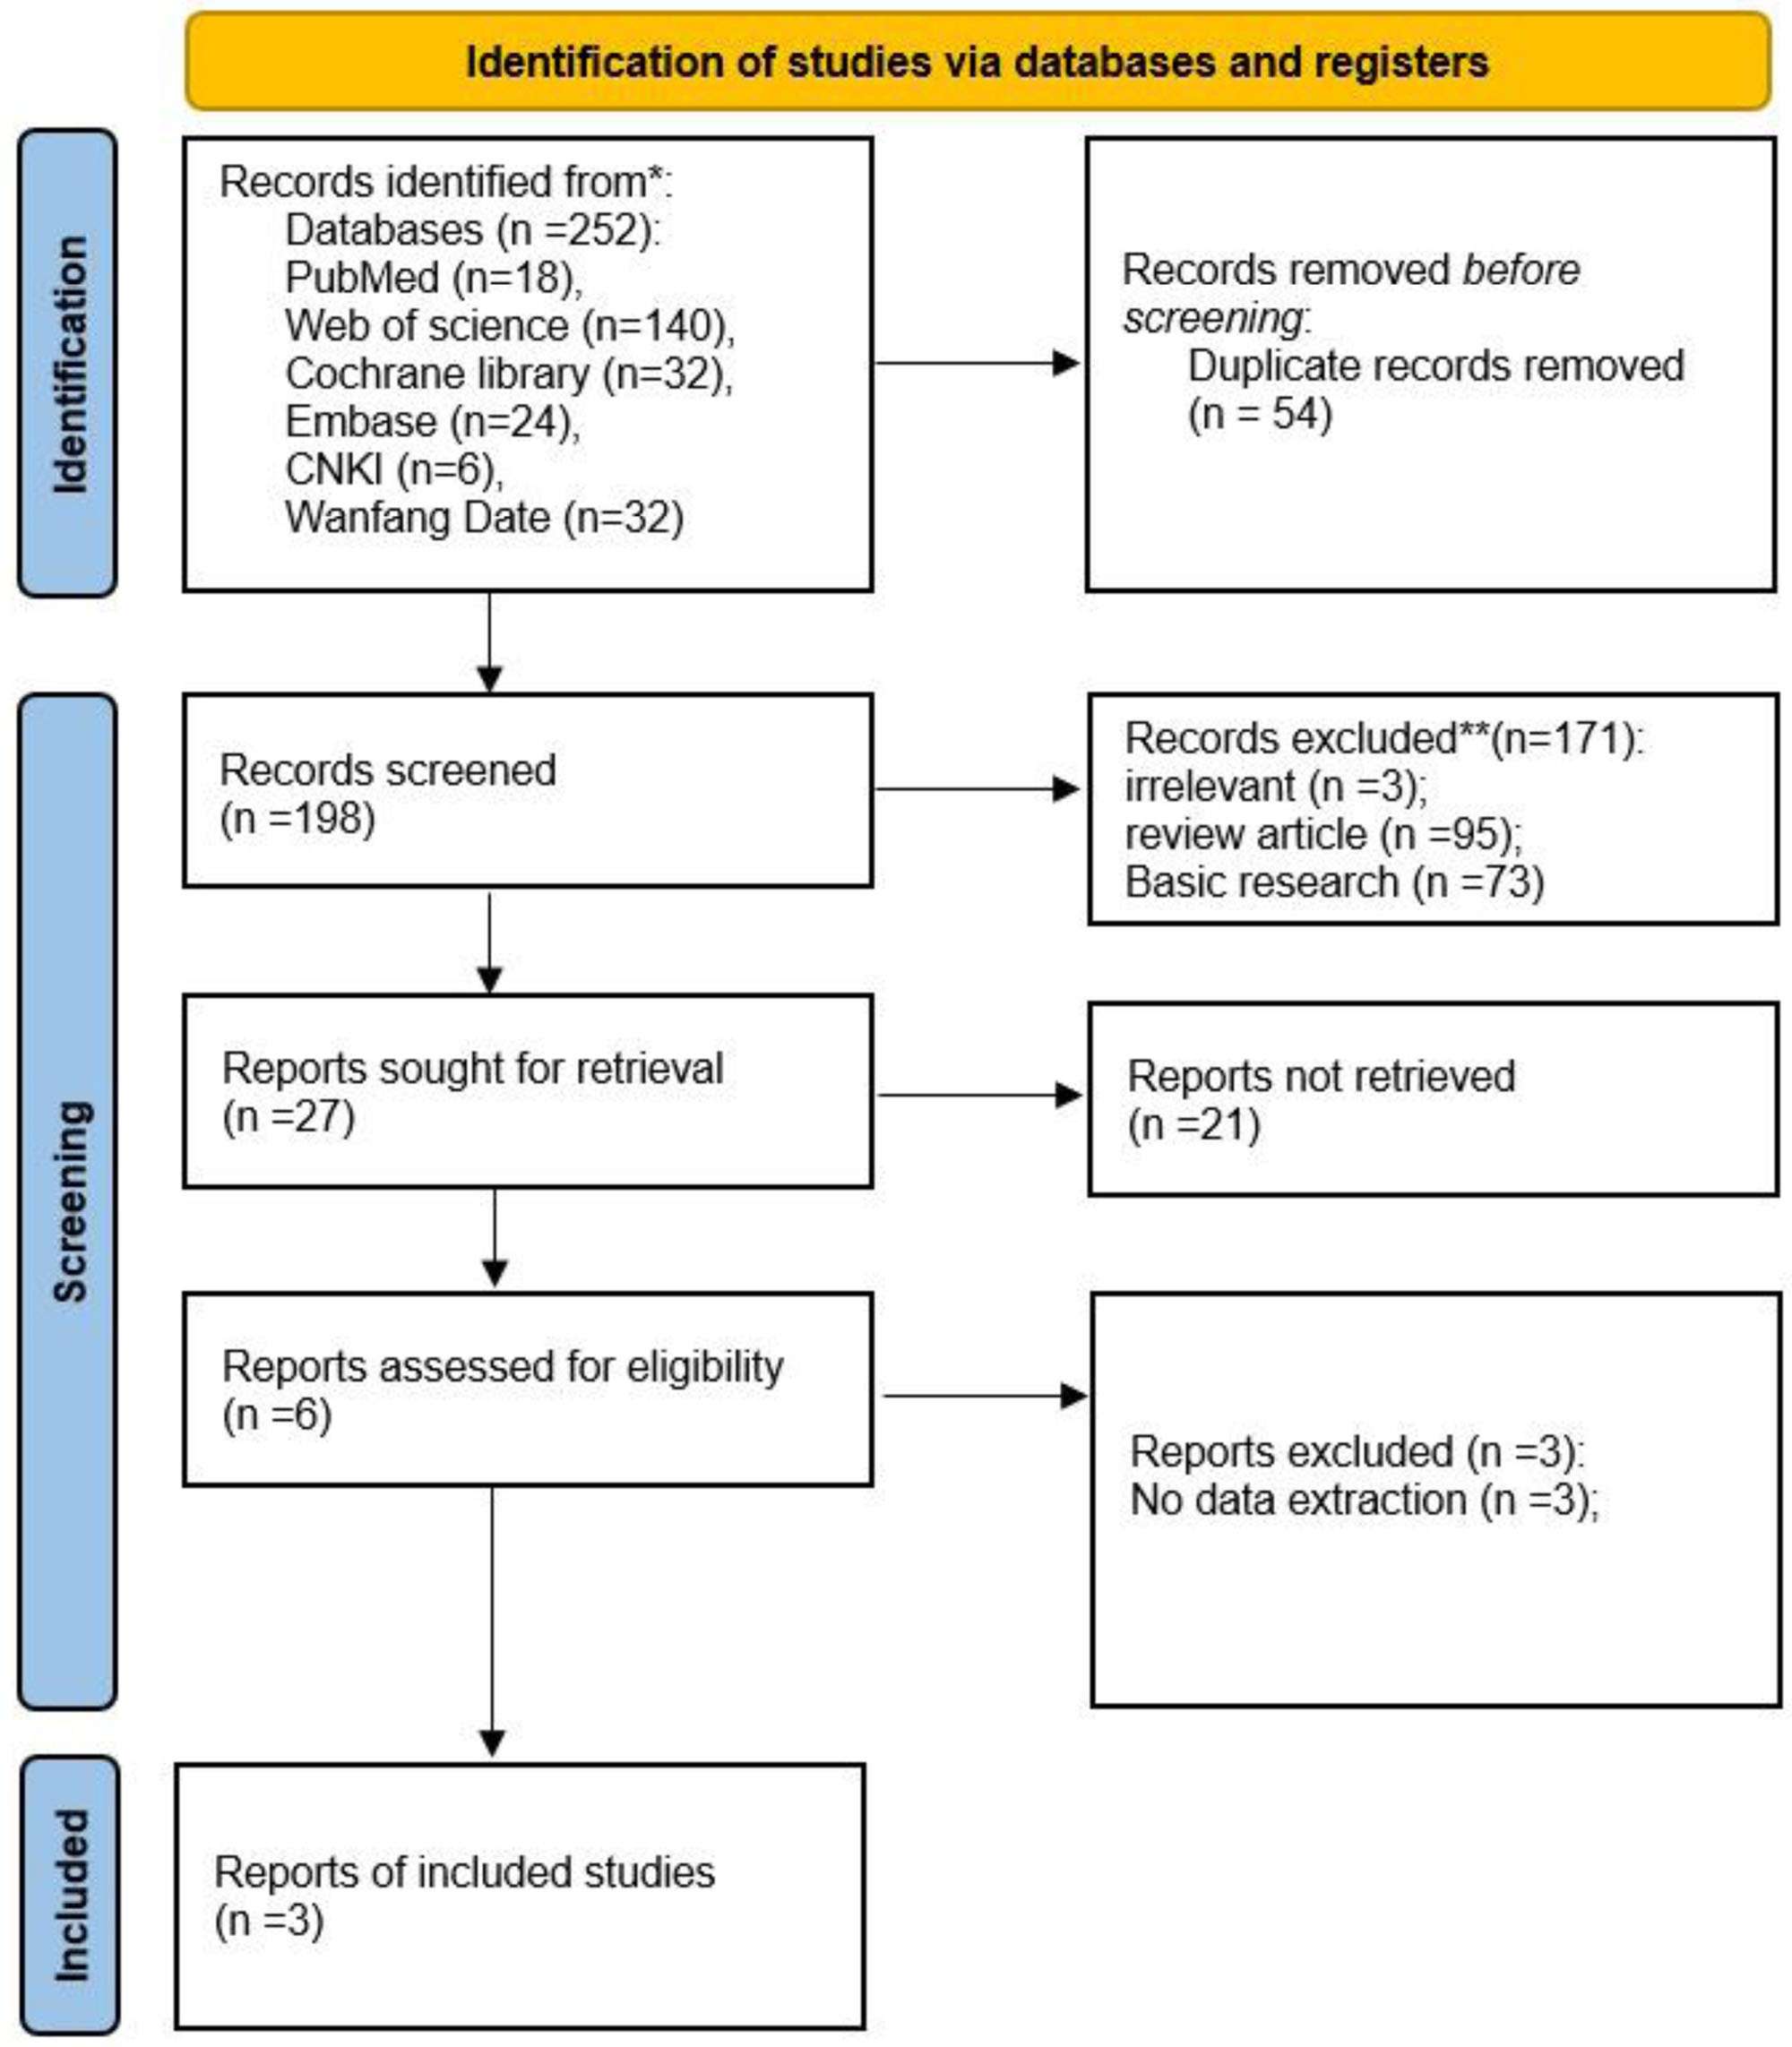

搜索結(jié)果:我們檢索了PubMed、Web of Science、Cochrane Library、Embase、中國(guó)知網(wǎng)、萬方等6個(gè)數(shù)據(jù)庫,共納入293篇與臍帶間充質(zhì)干細(xì)胞治療膝骨關(guān)節(jié)炎相關(guān)的研究,根據(jù)納入與排除標(biāo)準(zhǔn)納入3篇研究,最終納入3篇研究(圖1)。